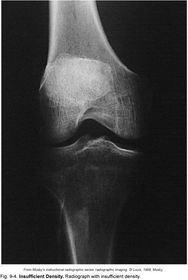

Insufficient Density image appears too bright (too many x-ray photons)